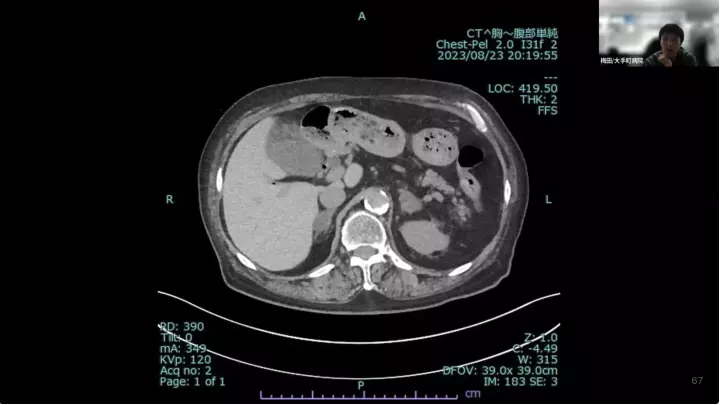

外科医目線の~急性胆嚢炎~治療編